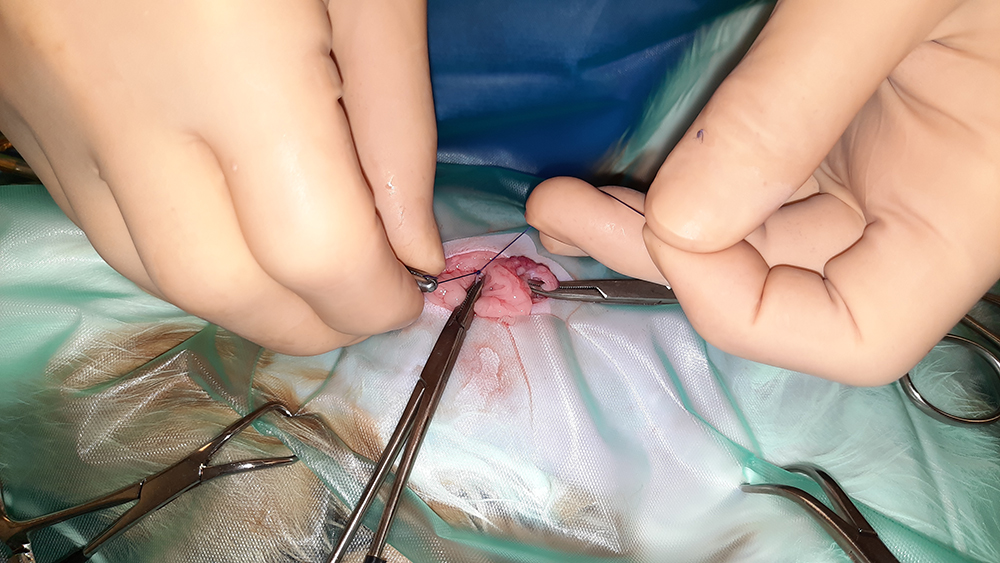

Er wordt een kleine snede gemaakt in de buik, ter hoogte van de navel. Vervolgens worden na elkaar de twee ovaria (=eierstokken) opgezocht, de aanvoerende bloedvaten afgebonden en de eierstokken verwijderd. Hierna wordt de buik in 3 lagen gesloten; de spierlaag, de onderhuid en de huid. Deze laatste wordt onderhuids gesloten met soms een enkele uitwendige knoophechting, zodat er zo min mogelijk hechtingen zichtbaar zijn. Er wordt een wondpleister geplaatst, nadat het wondgebied voorzichtig is schoongemaakt.